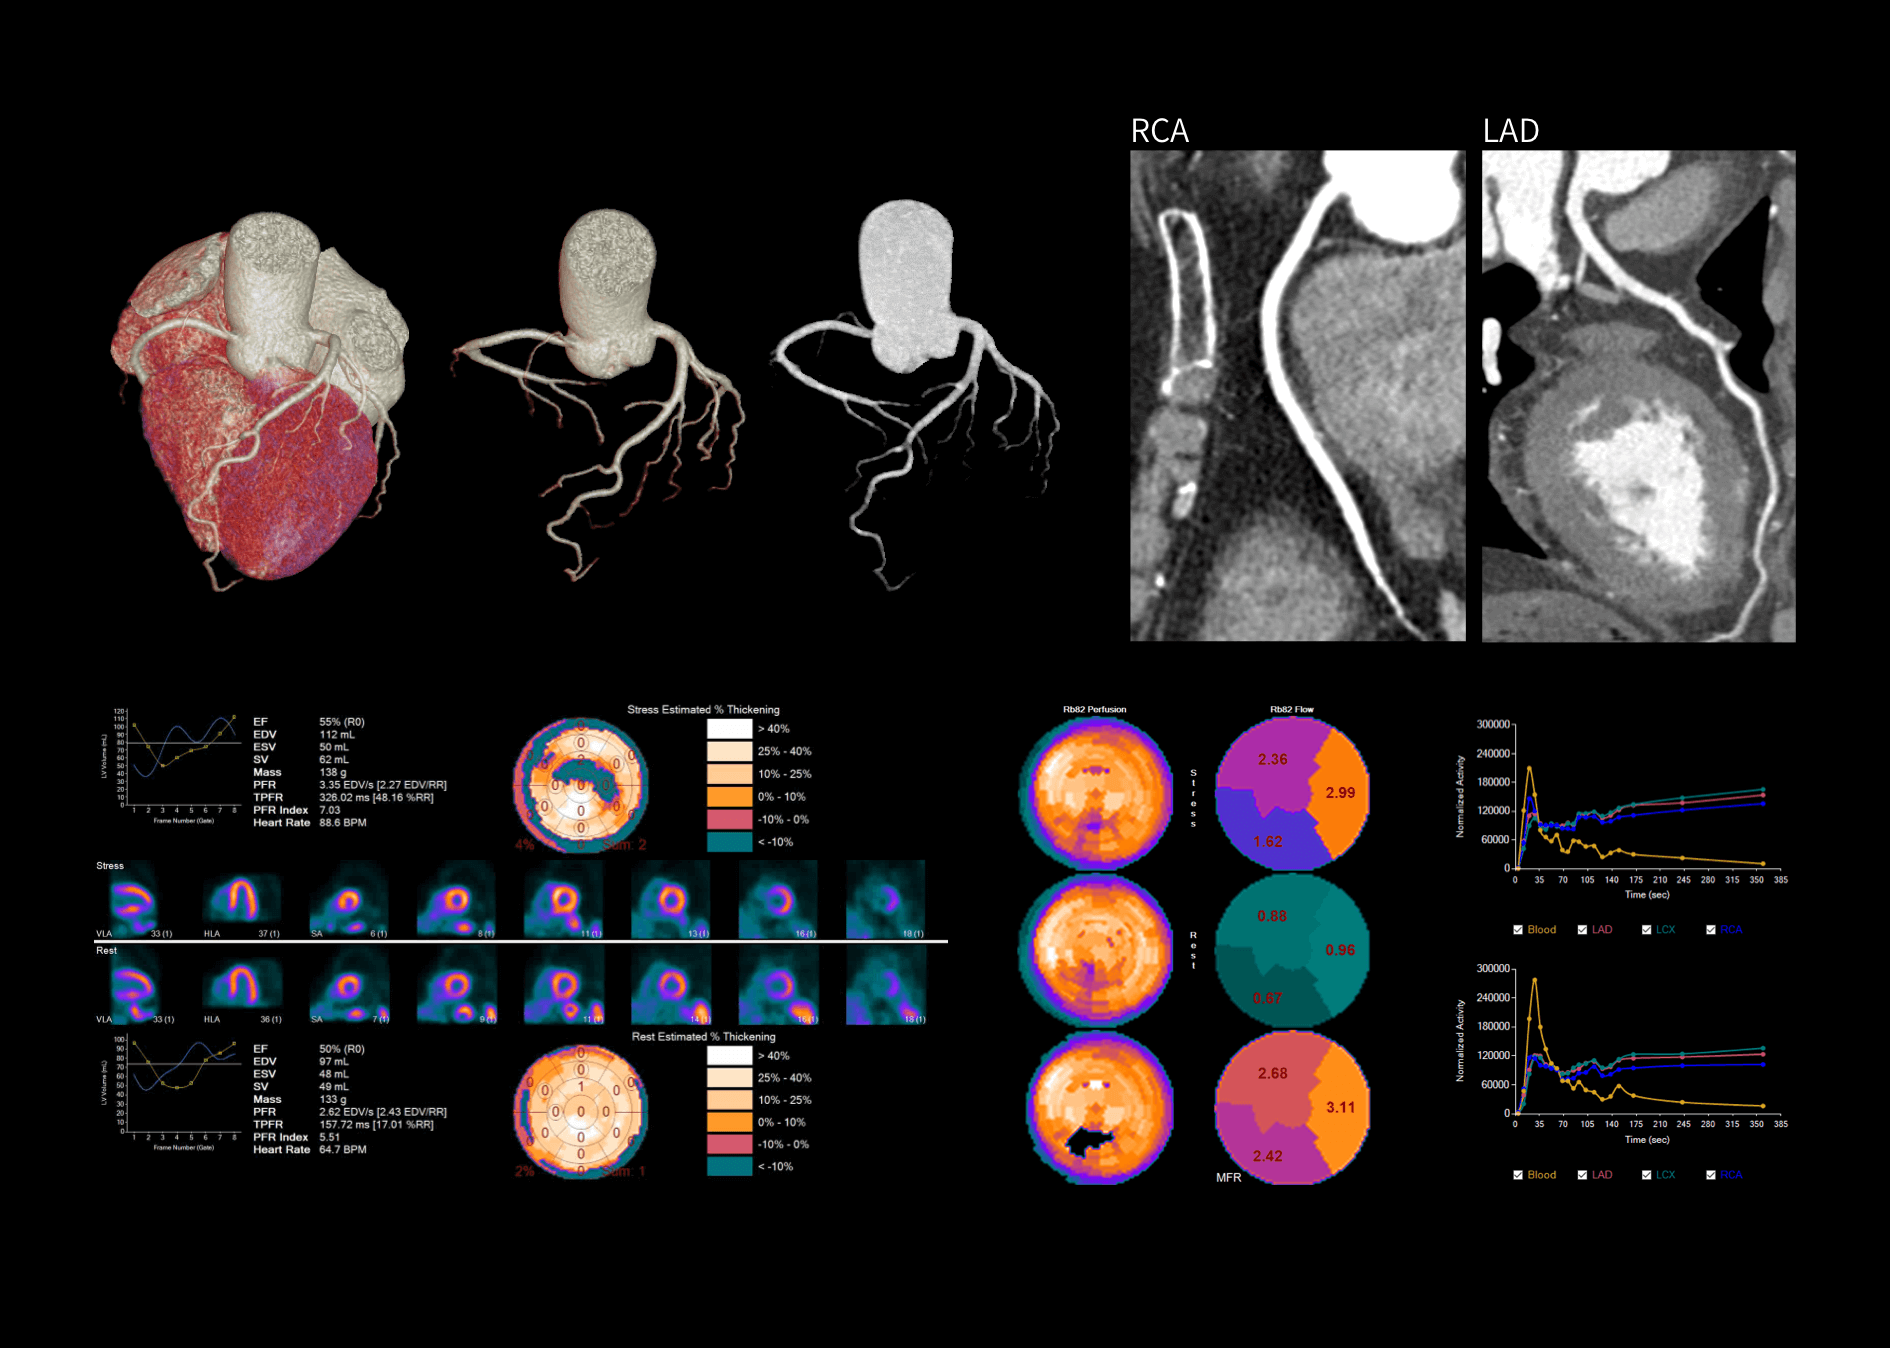

时空影像链数据源头提升CT图像质量

超高机架转速成就精准CT心脏扫描

从冠脉CTA到PET心肌灌注全套工作流

提供CT及PET全方位精准心脏功能评估*

*uWS-MI后处理工作站提供高级心分析应用